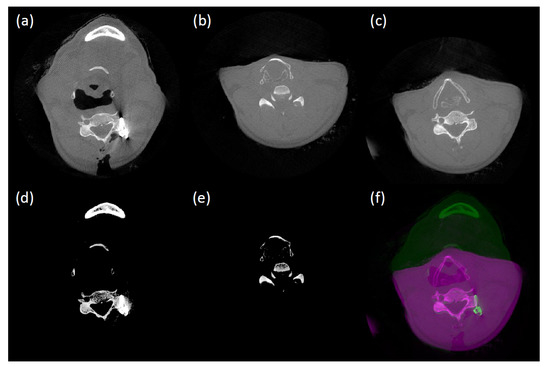

Figure 7 and Figure 8 show some results we obtained using our metal artifact reduction algorithm. The spine has two pedicle screws implanted. Figure 7 shows one of them in transverse, sagittal, and coronal views. Note that the sagittal and coronal views are horizontal and vertical cut slices passing through the screws, respectively. Figure 8 shows the other implanted screws in the same manner. Overall, the proposed method effectively removes the metal artifacts (dark/bright bands and streaks) and reveals clear outlines of the implanted pedicle screws, which are suitable for evaluating their placements after the surgery. For example, in Figure 7 (top and bottom rows), the yellow arrow indicates a pedicle screw where only the corrected image (Column b) can reveal that is has been correctly inserted into the bone without extending into the tissue. Likewise, the yellow arrow in the middle row in Figure 7 shows a volume feature that was previously hidden by the beam hardening artifacts (Column a) but is now readily visible.

One side effect of the proposed method is the tendency of blurring the anatomical structures near metal objects. The difference images (Column c) between the uncorrected and corrected images show: (1) the removed artifacts; (2) a bright version of the metal pieces (as mentioned, our method lowers their projection values in the sinogram); and (3) some incorrectly removed details. The latter causes the blurring effects (annotated by the red arrow in Figure 7 and Figure 8). We think this is primarily because of the distance-based artifact region prediction model in Equation (6) where the model estimates the artifact regions based on the distance ( p i d t ) from a point to the nearest metal boundary along a ray path regardless of whether the point is corrupted by metal artifacts or not. One way to mitigate the blurring effect is by adding an additional stage at the end of our MAR framework to exploit the information hidden in low- and high-pass filtered sinogram [36] or images [37].

Figure 7. Case Study I. From top to bottom, transverse, coronal, and sagittal views. (a) uncorrected images, (b) corrected images, (c) uncorrected - corrected (a,b).

Figure 8. Case Study II. From top to bottom, transverse, coronal, and sagittal views. (a) uncorrected images, (b) corrected images, (c) uncorrected - corrected (a,b).